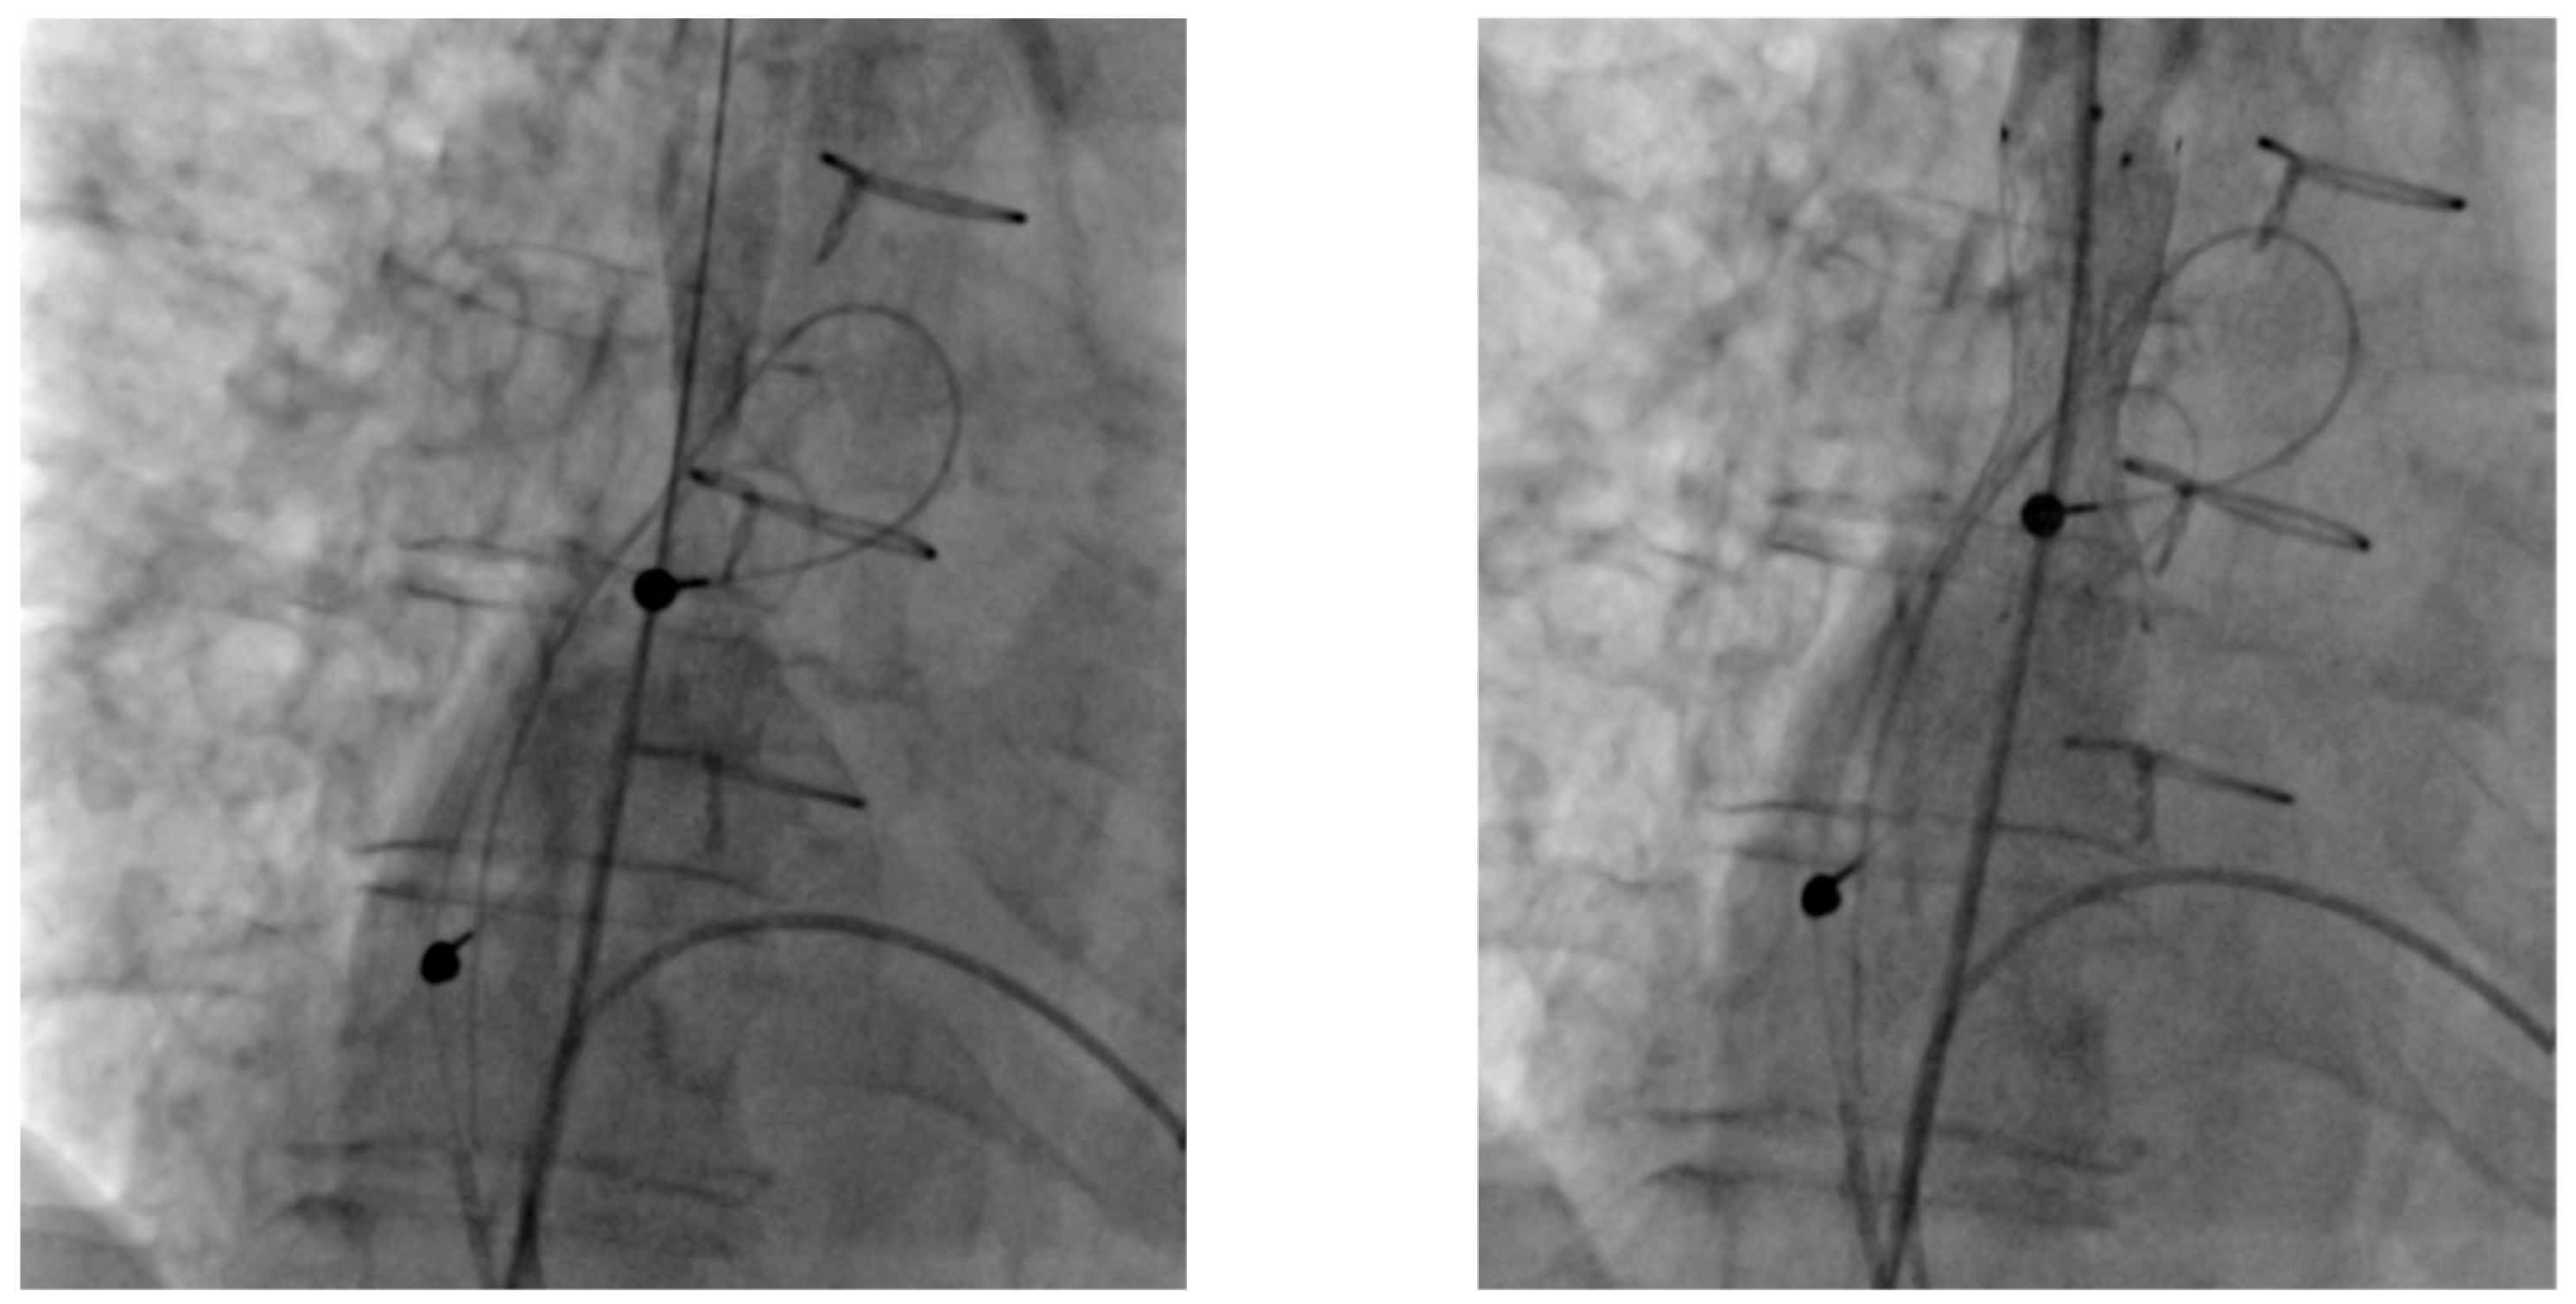

| 3 | 2-chamber pacemaker → CRT upgrade | HFmrEF, increased ventricular pacing | Left subclavian vein occlusion | Recanalization and PTA via axillary/brachial vein | Reocclusion next day |

| 7 | 2-chamber pacemaker → CRT-D upgrade | LVEF deterioration, increased ventricular pacing | Right subclavian vein stenosis | Right subclavian PTA via axillary/brachial vein | CRT-D upgrade successful |